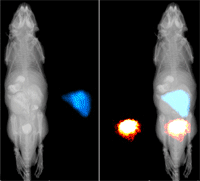

培訓期間,公司幾款2010年全新上市的儀器受到廣大經銷商及產品技術專業人員的關注與好評。其中,高清晰立體成像的多模式小動物活體旋轉系統實現了真正的三維成像,能夠更加精準地定位發光信號在動物體內的空間位置,使活體成像技術達到一個新的高度;全新的全自動多色熒光化學發光系統GL2200 Pro在傳統的高分辨率成像系統基礎上采取了全自動12.5-75mm 6倍變焦鏡頭。